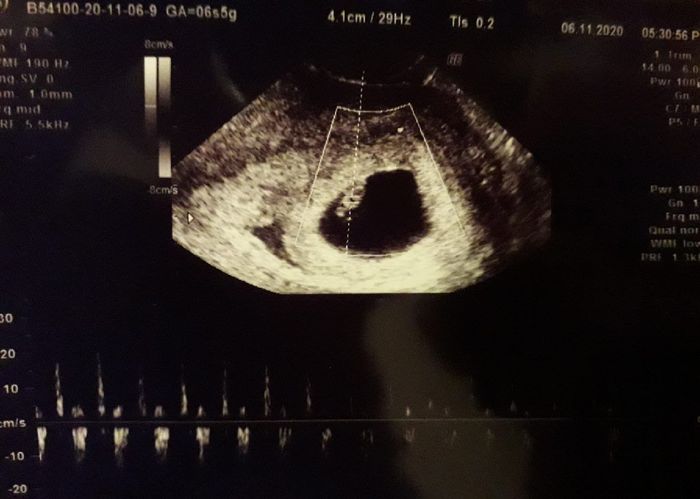

Ciao a tutte mamme ❤ ieri prima visita a 6+5 e sono riuscita a vedere il mio piccolino e a sentire il suo cuoricino...che emozione Volevo condividere questo momento così speciale con voi, anche se il periodo storico in cui ci troviamo ci abbatte e ci...